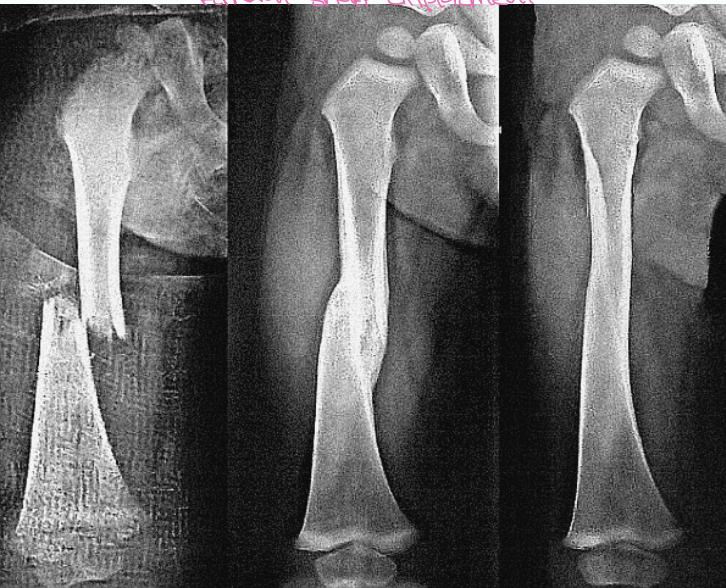

Femoral Shaft Displacement Example

“We accept it in children, but in adults we don’t”